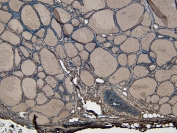

IHC staining of FFPE human liver cancer tissue with PC-1 antibody. HIER: boil tissue sections in pH8 EDTA for 20 min and allow to cool before testing.

IHC staining of FFPE human placental tissue with PC-1 antibody. HIER: boil tissue sections in pH8 EDTA for 20 min and allow to cool before testing.

IHC staining of FFPE human endometrial cancer tissue with PC-1 antibody. HIER: boil tissue sections in pH8 EDTA for 20 min and allow to cool before testing.